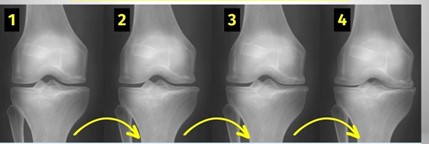

1. Radiografia

É o exame fundamental: mostra estreitamento articular, osteófitos e deformidades.

Deve ser efectuado sempre em carga para não subestimar o desgaste.